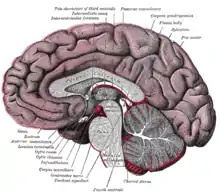

Contrairement aux feuillets plus externes (arachnoïde et dure-mère) qui suivent l’endocrâne, la pie-mère dans sa partie cranienne épouse étroitement le relief du parenchyme en suivant les sillons, scissures et circonvolutions du cortex cérébral, ce qui fait que sa surface est beaucoup plus importante que celles des autres méninges qui sont tendues au-dessus des renfoncements du tissu nerveux. Les espaces ainsi formés entre la pie-mère et l’arachnoïde sont appelés espaces sous-arachnoïdiens ; certains sont plus largement dilatés en ce qu’on appelle des citernes sous-arachnoïdiennes, elles sont situées à la base du crâne principalement autour du tronc cérébral. Les espaces sous-arachnoïdiens sont remplis de liquide cérébrospinal anciennement appelé liquide céphalo-rachidien (LCR) et traversés par des trabéculations ou travées arachnoïdiennes qui attachent la pie-mère à la face interne de la membrane arachnoïde.

Une coupe des différents méninges. Coupe sagittale médiane du cerveau.